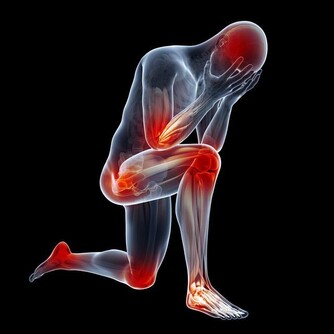

腳雖然位於人體最低處,但它是身體健康的“指向標”之一,所以才有“百病始於腳,養生先養腳”的說法。

腳上出現這4個信號,說明你的肝越來越差!